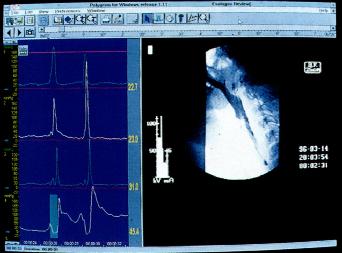

同步吞钡透视及测压检查(图2.5)

为评价吞咽异常可同步进行咽部测压及X线透视。钡透视显影与生理指标记录同步进行,检测同步显示,并以数字方式记录在同一计算机上。

同步钡透及测压检查

图2.5同步钡透及测压检查(图取自Medtronic GastroIntestinal).

X线电视诊断

可显示钡剂通过咽部的情况并确定其是否流入气道。与咽部测压联合进行可对咽部功能紊乱的发病机制进行详细分析,效果优于单独行上述二种检查。